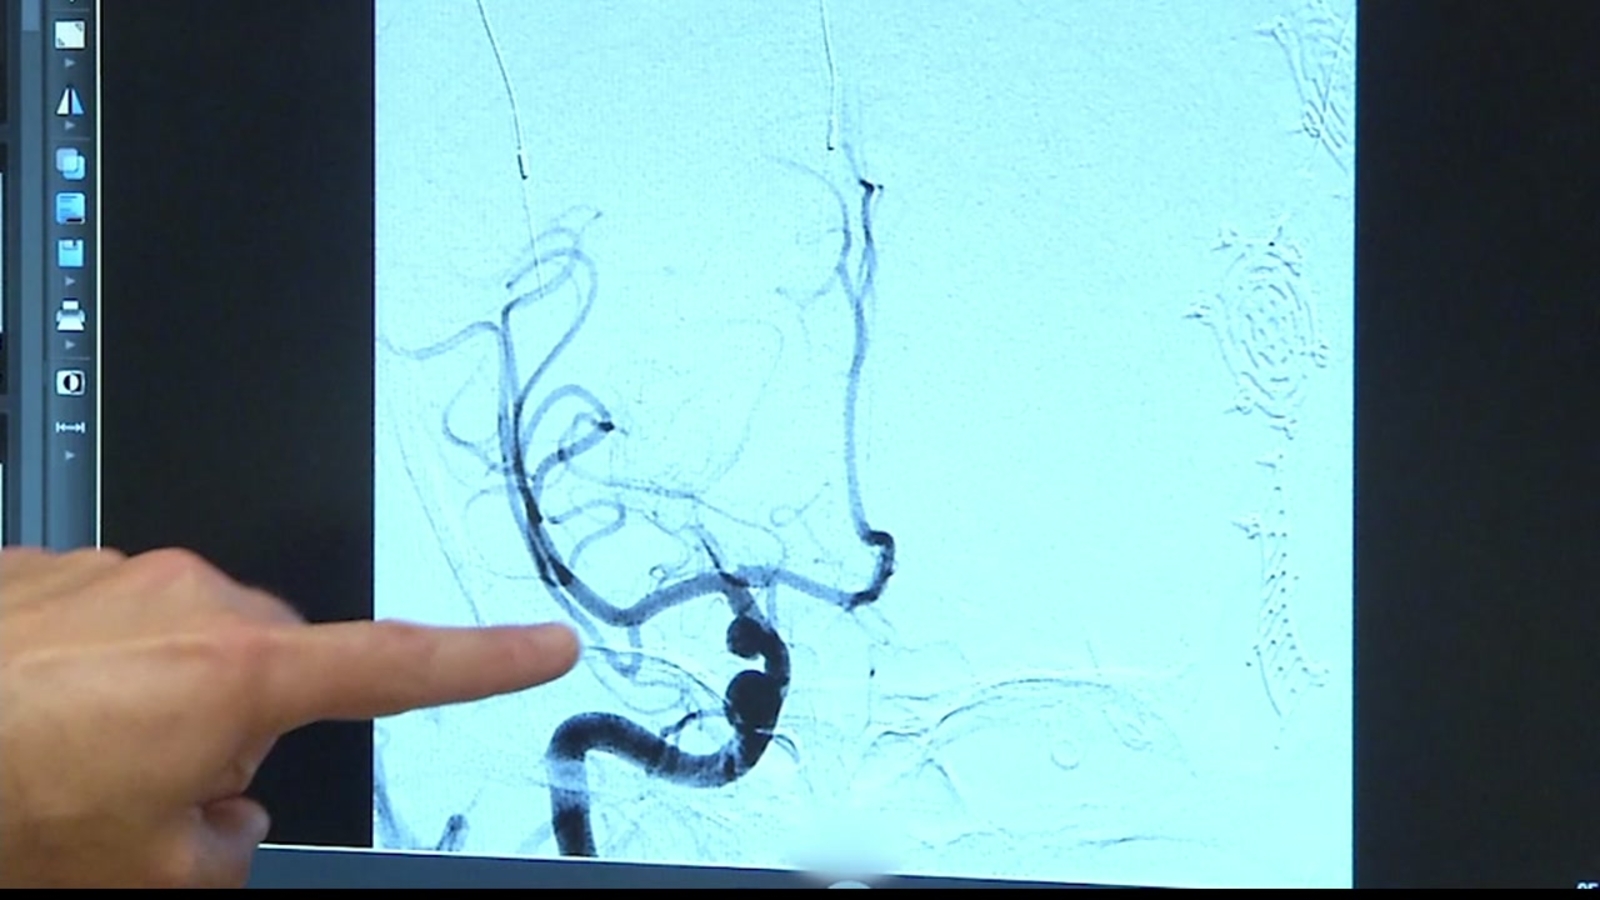

The award-winning stroke program at Washington Hospital concentrates on every facet of stroke management from emergency room entry to discharge. The team of specialists, physicians, and nursing professionals work efficiently to diagnose and quickly treat patients, as expert action within the first hours of a stroke is critical. If you suspect that you or a loved one is having a stroke, do not delay and call 911.